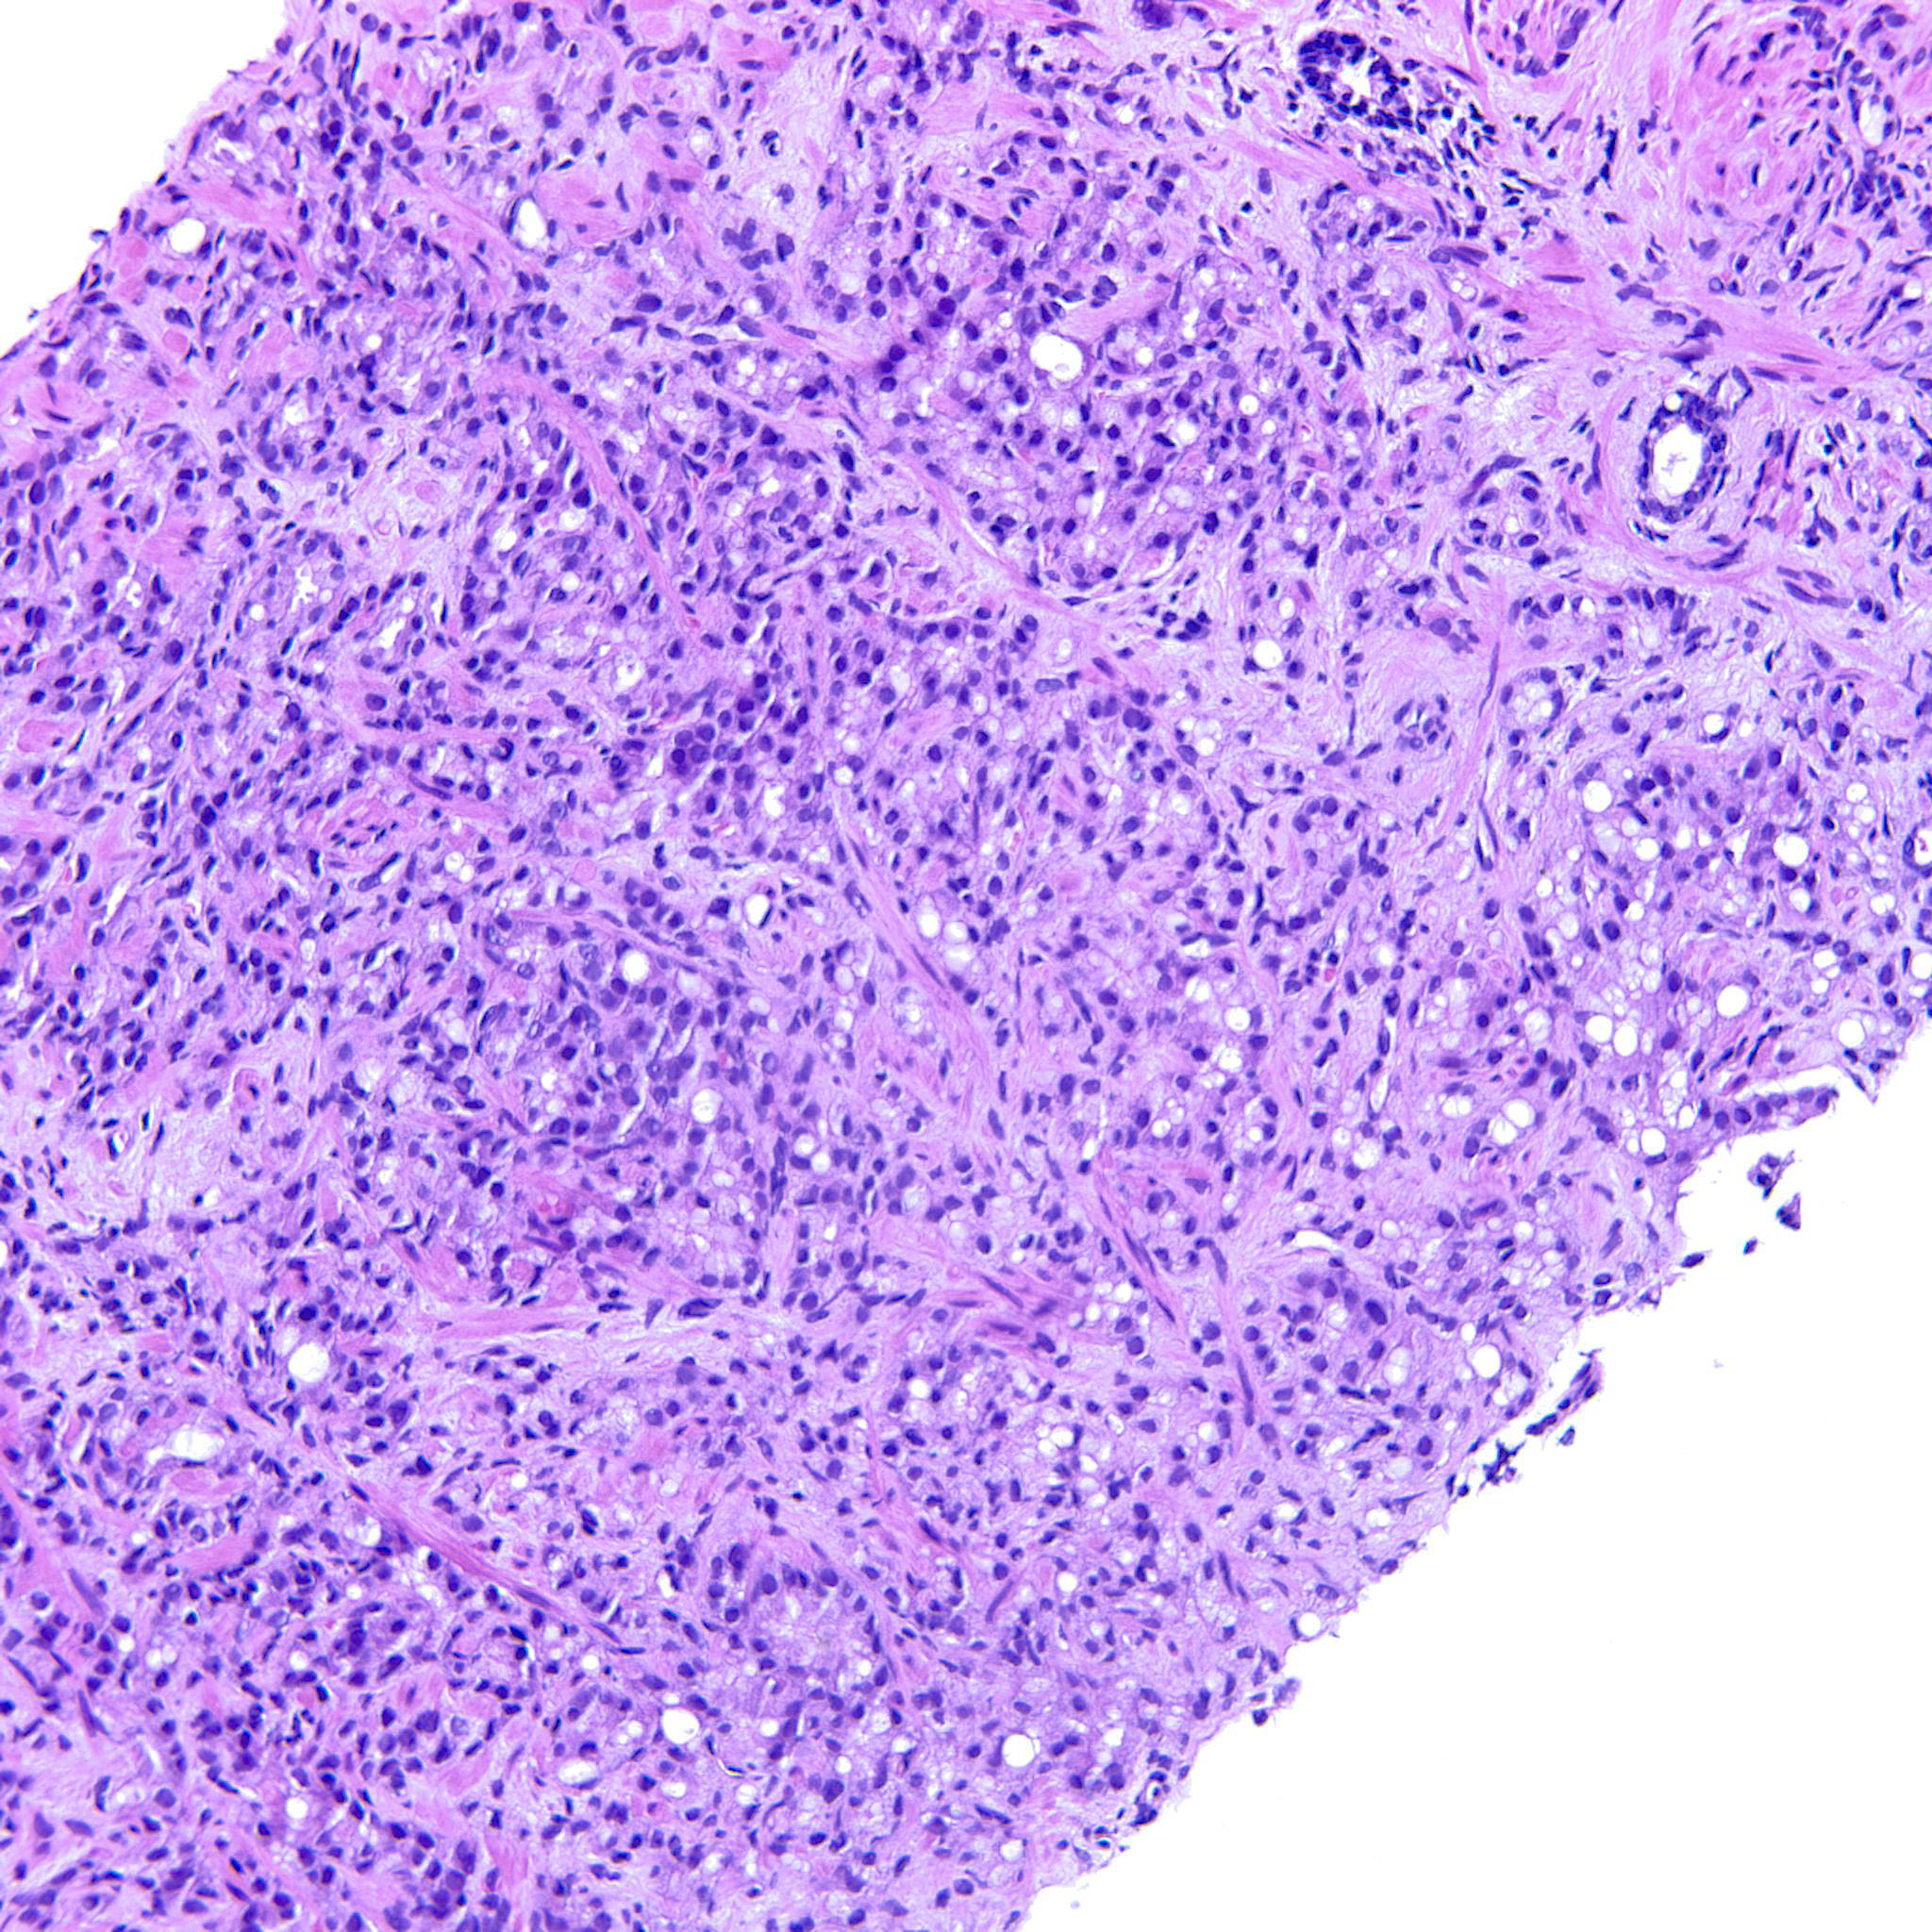

Prostate cancer grading

Case ID: 744